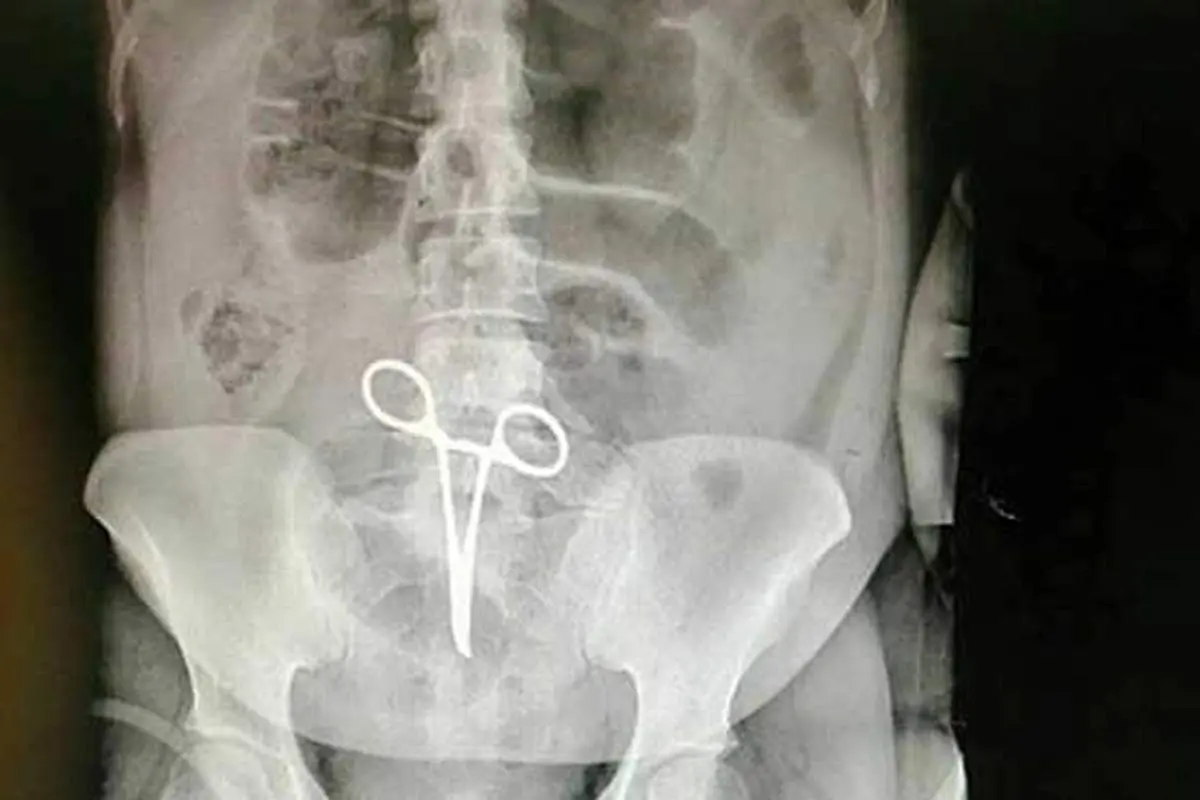

جا ماندن پنس 22 سانتی داخل بدن زن بیمار!

بیماری که پنس جراحی داخل بدنش جا مانده بود 10 روز بعد به دلیل درهای شدیدی که احساس می کرد دوباره به بیمارستان مراجعه کرد تا اینکه با بررسی ها و عکسبرداری های دقیق روشن شد یک پنس 22 سانتی متری داخل بدنش جا مانده است و جراح بعد از پایان عمل فراموش کرده تا او را بردارد.